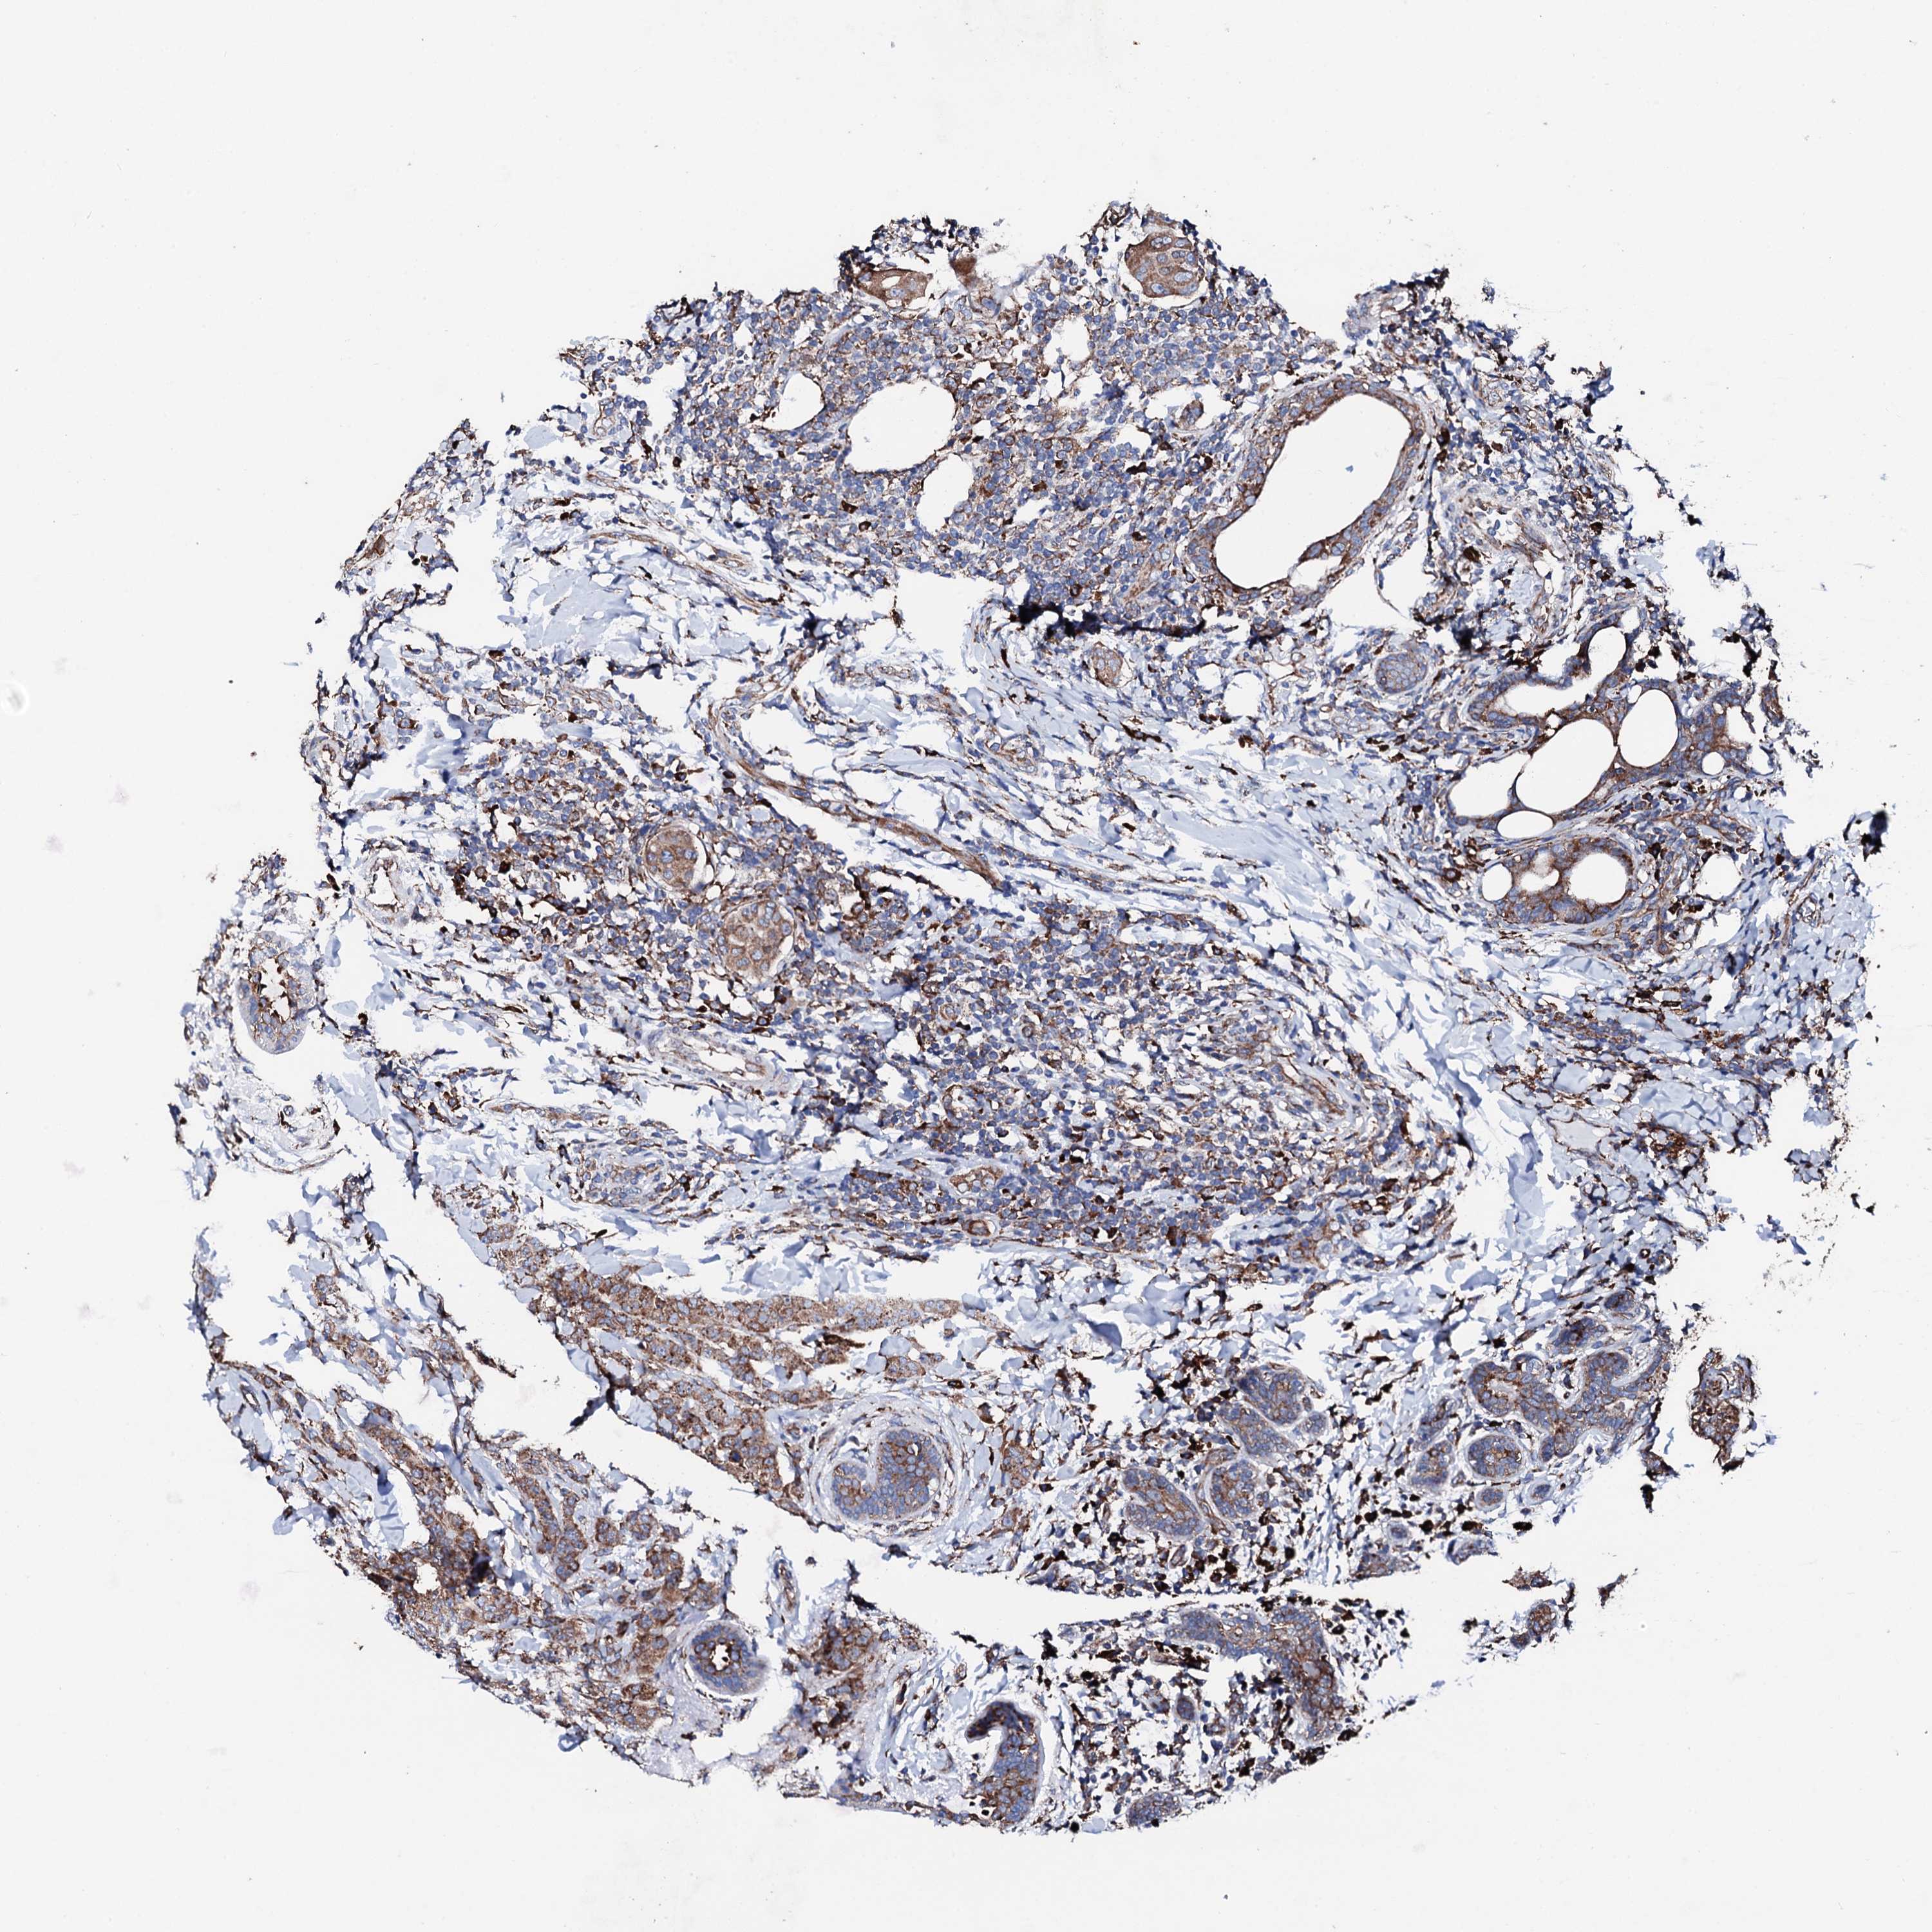

CANCER BREAST CANCER Show tissue menu

BRCA TCGA BRCA VALIDATION PROTEIN EXPRESSION